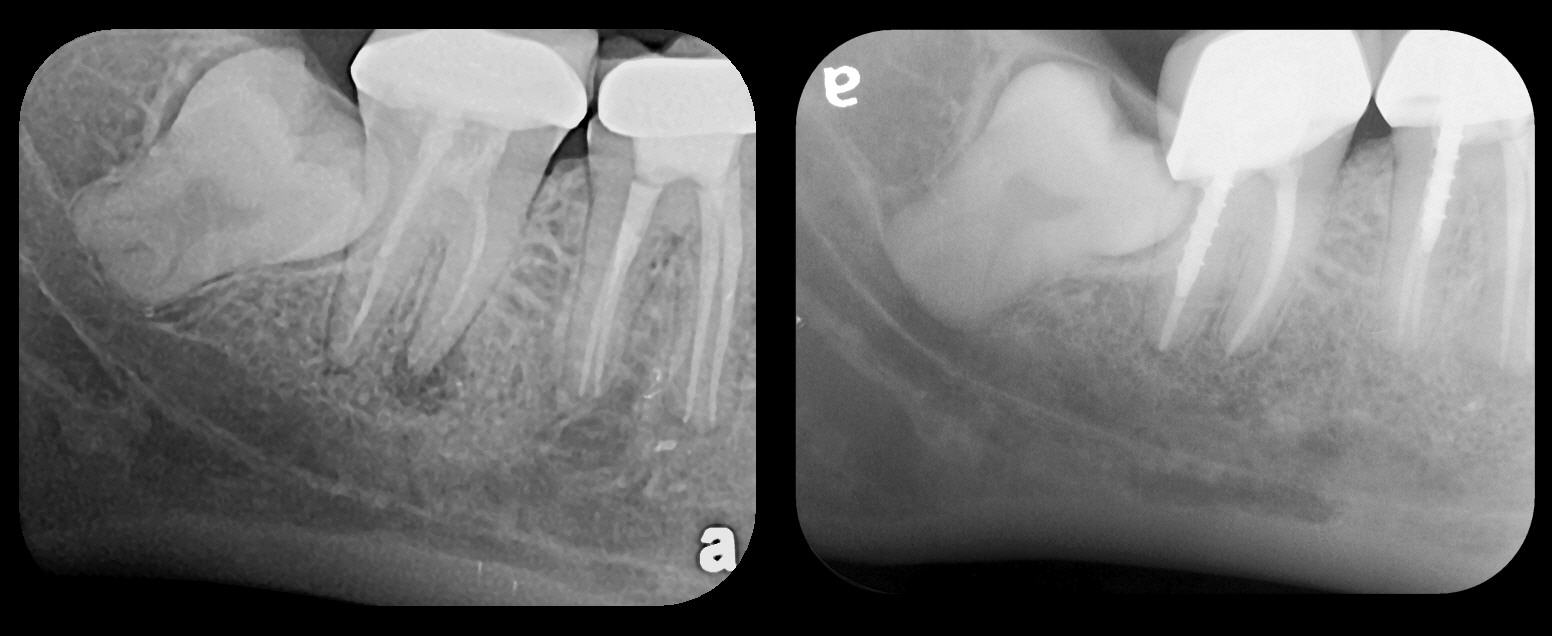

In a case where a patient is unable to tolerate the correct placement of an HW sensor, either due to anatomic or behavioral reasons, in a location that will allow viewing the apex of a tooth to receive endodontic treatment, and subsequent post-obturation visits are periodically scheduled to follow the long-term outcome of the procedure, the inability to visualize an advancing PA lesion may constitute a charge of supervised neglect (Figure 11). The definition of supervised neglect is "a situation where a patient's oral health has been allowed to deteriorate over a period of time, despite regular attendances to the dentist who is responsible for the patient's care and treatment."21 Use of easily tolerated PSP radiographs in this instance would likely eliminate the potential legal difficulty by allowing the clinician to properly make the patient aware of any observed pathosis (Figure 12).

Fig 5. Bilateral concerns for this patient are evident on these PSP

radiographs. Tooth No. 17 may exhibit pathology distal to the root. In

addition, extreme length of root of tooth No. 32 through the entire height

of the body of the mandible is cause for concern if extractions of Nos.

17 and 32 are planned. Three-dimensional CBCT study and alerts to

the patient as to the potential surgical complications on extractions are

required in this instance. There is no benefit to panoramic radiography

in this case.

Figure 5